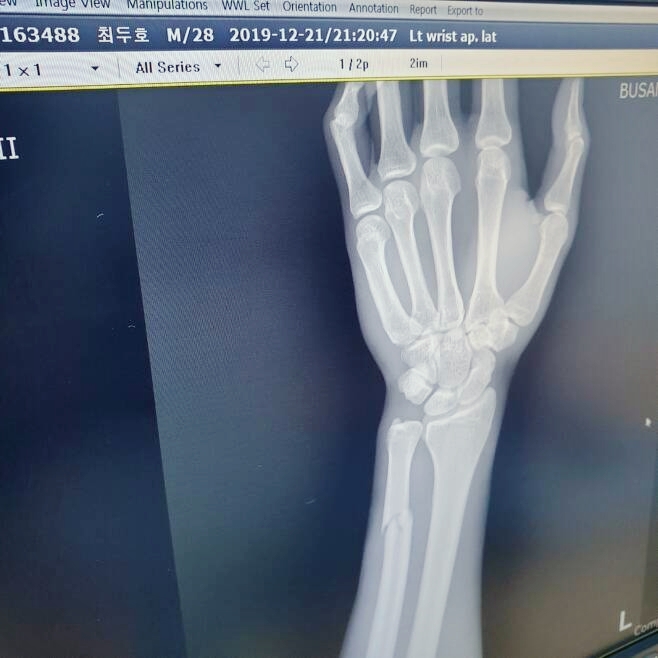

팔목 골절도 있으니, 빨리 쾌유하고

소속팀 팀매드는 경기 후 SNS를 통해 최두호의 부상 소식을 전했다. “최두호는 1라운드 초반에 왼팔 손목이 부러졌다”라고 글을 남겼다.